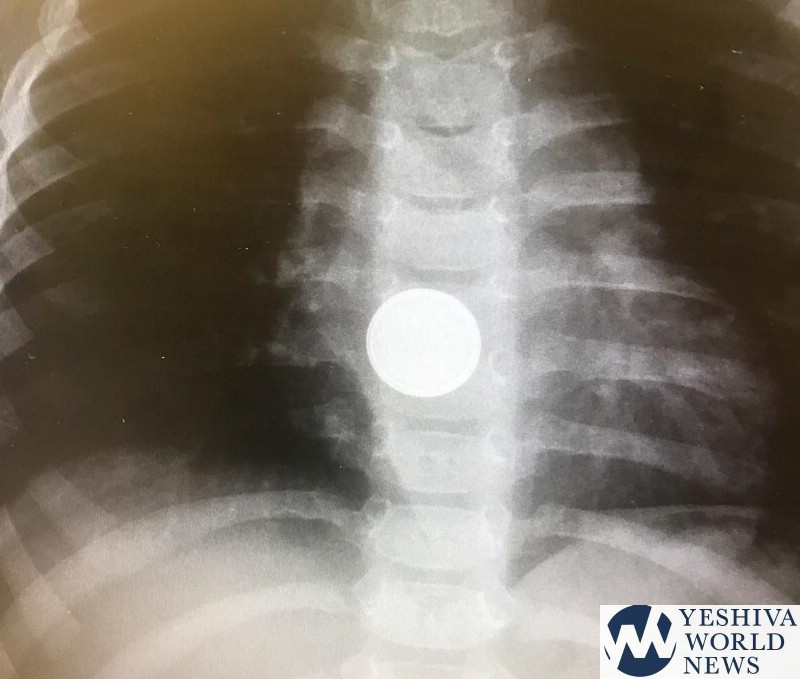

A few weeks ago, a child arrived after swallowing a battery, and it was stuck in her esophagus, endangering her life. The battery was removed endoscopically. However, the battery, which was only lodged in the esophagus for two hours, had already caused severe burns that required multidisciplinary involvement of pediatric, gastroenterologists, dermatologists, ENTs and chest surgeons. The girl was released to her home in good health about a month later.